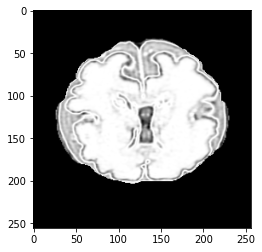

An image is converted into an intuitionistic fuzzy form, denoted as BIFSB^{IFS} to handle uncertainty in transition regions, thereby enabling better pixel classification. Image features are represented by membership, non-membership, and hesitation degrees. The CNNs for image classification utilise these intuitionistic fuzzy representations for improved feature extraction. The hesitation component highlights boundary regions, offering additional information for feature analysis. Higher hesitation values indicate more uncertainty, while zero hesitation reflects clear membership or non-membership. The membership and non-membership values define the degree of belonging or non-belonging for each pixel, and their distributions are illustrated in Fig.1.

Refer to caption

(a)

(b)

(c)

Figure 1: Intuitionistic fuzzy data in form of (a): membership, (b): non-membership and (c): hesitation degree.